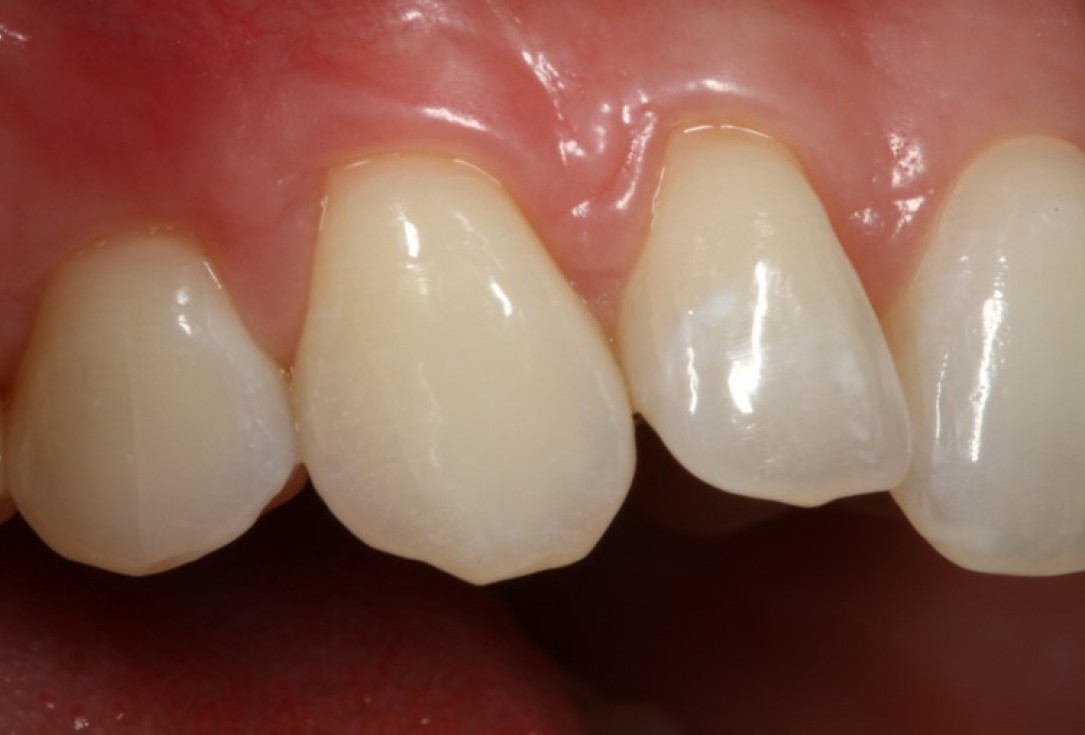

06/06 - Clinical situation 18 months post-operative.Multiple gingival recessions treated with the modified coronally advanced flap in conjunction with mucoderm® - Prof. Dr. Dr. A. Kasaj